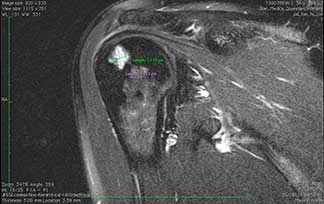

Artroscopia

de hombro

Permite ver la articulación del hombro a través de tres portales menores a un centímetro de diámetro lo cual permite corroborar los diagnósticos y aplicar tratamientos curativos ya que la mayoría de las estructuras del hombro son accesibles por artroscopia. Es una técnica mínimamente invasiva para acceder a los dos compartimentos de la articulación la glenohumeral y subacromial.

Es una opción de tratamiento en las patologías del manguito rotador (supraespinoso, subescapular, infraespinoso y redondo mayor), tendinitis de la porción larga del biceps, compresiones subacromiales, inestabilidad glenohumeral y algunos tipos de fracturas o luxaciones.